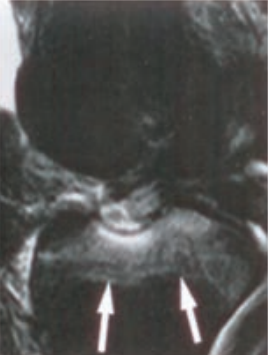

Jakie struktury anatomiczne uwidoczniono na obrazie USG?

Ilustracja do pytania 33

A. Pęcherz moczowy z kamieniami.

B. Ciężarna macica z czterema płodami.

C. Nerka lewa ze złogami.

D. Pęcherzyk żółciowy z kamieniami.